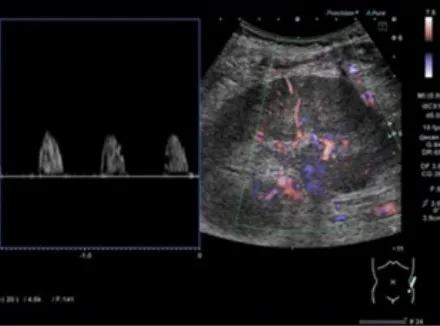

Uma causa incomum de hematúria glomerular intermitente!

Hematúria pós infecção, caso clínicos para auxiliar no entendimento de causas glomerulares comuns e raras...